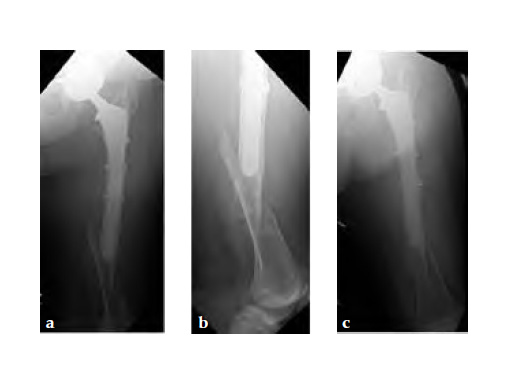

Case 1: A 78-year-old female sustained a periprosthetic fracture, Vancouver type C, 9 years after a total hip arthroplasty.